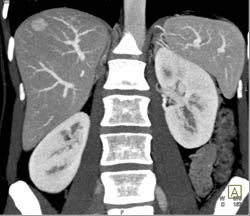

Focal Nodular Hyperplasia (FNH)